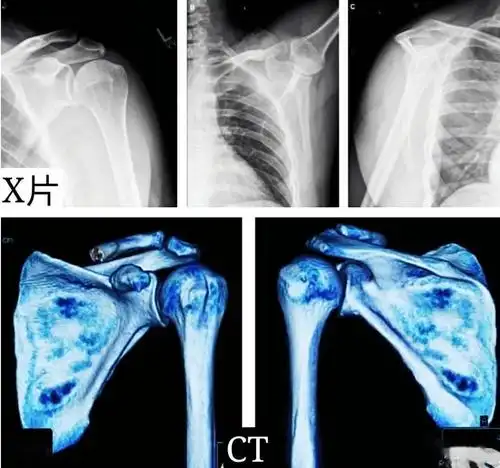

术前左肩关节正位片提示:左肱骨大结节处骨赘形成(肩峰撞击引起)

术后右肩关节正位片